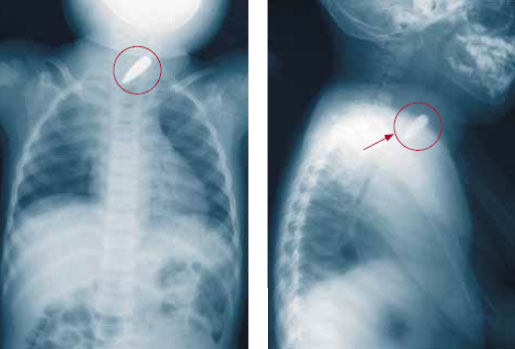

Очевидно, что если в процессе иссечения раны хирург обнаружит ранящий снаряд, то он должен его удалить. Однако не следует рассекать здоровые ткани в поисках такого снаряда. Тем не менее есть два условия, при которых требуется немедленное удаление пуль и осколков, и эти условия связаны с подтвержденными практикой рисками и осложнениями.

Рисунок 4. Пуля в верхнем средостении

Проводить ли удаление в срочном или плановом порядке, будет зависеть от анатомической локализации инородного тела и от того, какая структура подвергается опасности, от гемодинамической стабильности пациента, наличия диагностического и операционного оборудования и, что самое важное, от квалификации хирурга. Риски, связанные со сложной процедурой (удалением пули из средостения, головного мозга и т. д.), при которой процент осложнений может быть весьма высоким (особенно в неопытных руках), необходимо сопоставить с преимуществами отказа от такой процедуры, имея в виду, что общая частота осложнений при отказе низка. Более подробно показания к удалению будут рассмотрены отдельно.